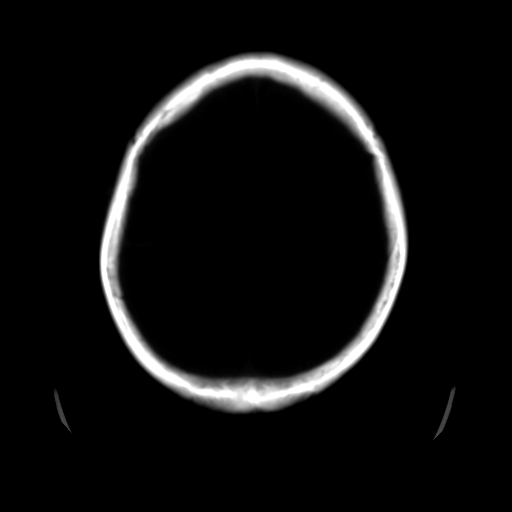

标题: CT25225:男,51岁,头外伤一小时。 [打印本页]

标题: CT25225:男,51岁,头外伤一小时。

男,51岁,头外伤一小时,呕吐两次。

蛛网膜下腔出血 脑肿胀

左侧颞部硬膜外;蛛网膜下腔出血 ;脑肿胀

1)左侧中颅窝蝶骨翼后方硬膜外血肿。2)左侧颞顶部硬膜下血肿。3)蛛网膜下腔出血。4)左侧筛窦及双侧蝶窦炎症(或积血)。5)左侧额部头皮软组织肿胀。